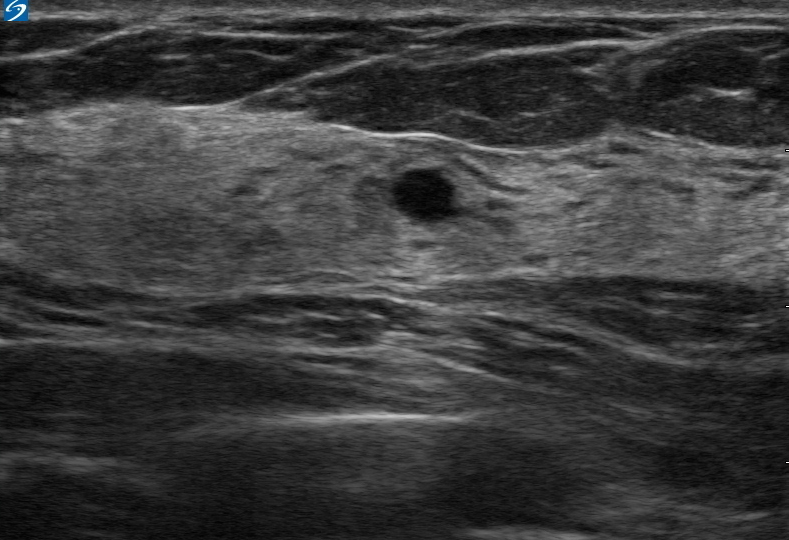

乳房嚢胞の画像